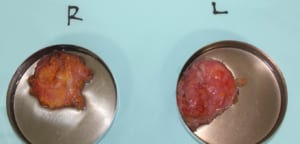

このモニターゲストに関しては、皮下脂肪はそれほど多くなかったものの、乳腺の発達が認められましたので真性女性化乳房と診断しました。

この女性化乳房モニターに行った施術は、ベイザー脂肪吸引と乳腺摘出

このモニターゲストに関しては、皮下脂肪はそれほど多くなかったものの、乳腺の発達が認められましたので真性女性化乳房と診断しました。